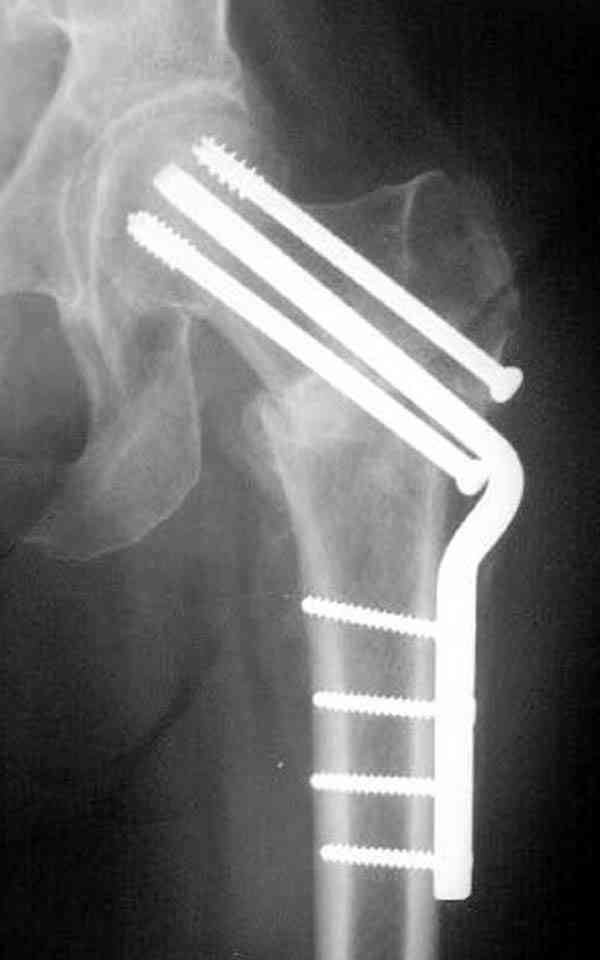

Коллега Челноков прав, здесь еще имеется риск перелома за счет ослабления латерального кортекса. Во время установки канюлированных шурупов за редким исключением спица вводится с одного раза, множественные попытки ослабляют латеральный кортекс, что станет источником перелома в этом месте.

В идеале для профилактики рефрактуры шурупы надо вводить не больше, чем под 130 градусным углом и не ниже уровня малого вертела.

Здесь случай перелома из-за ослабления латерального кортекса через 3 недели после операции на шейке. Шурупы были установлены под большим углом, слабый латеральный кортекс не выдержал нагрузку.